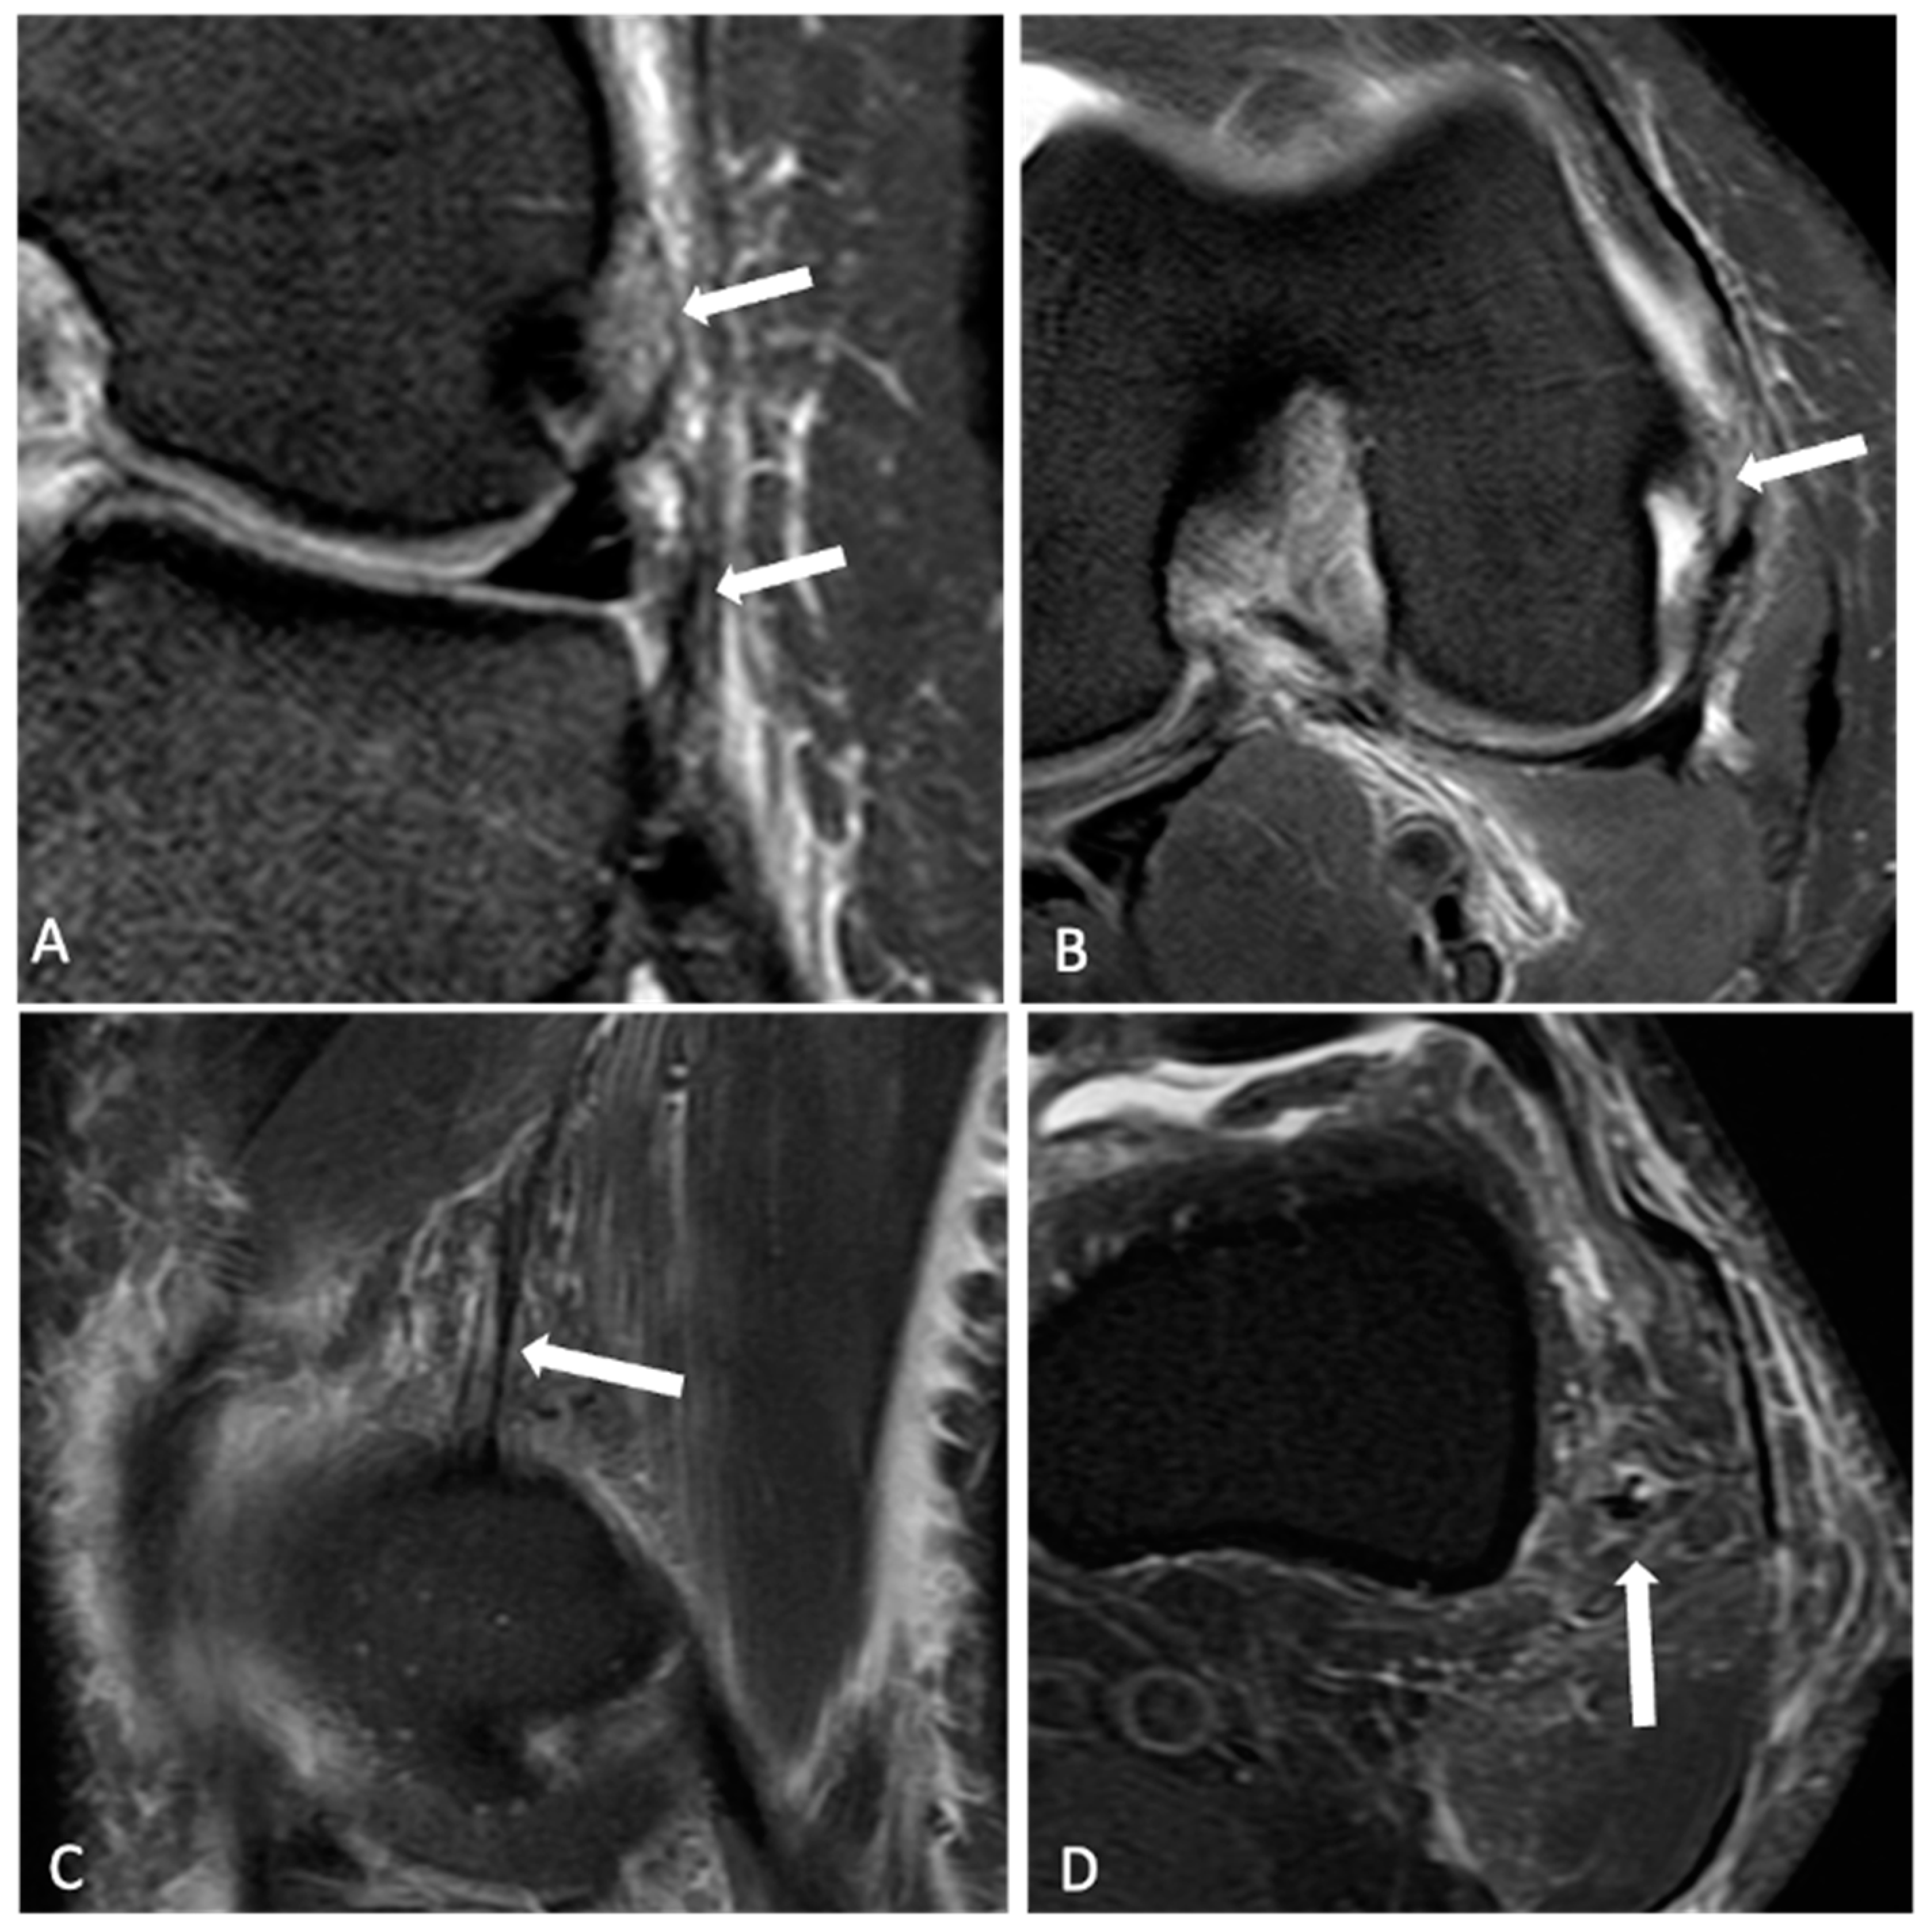

2.2. Radiological Analysis